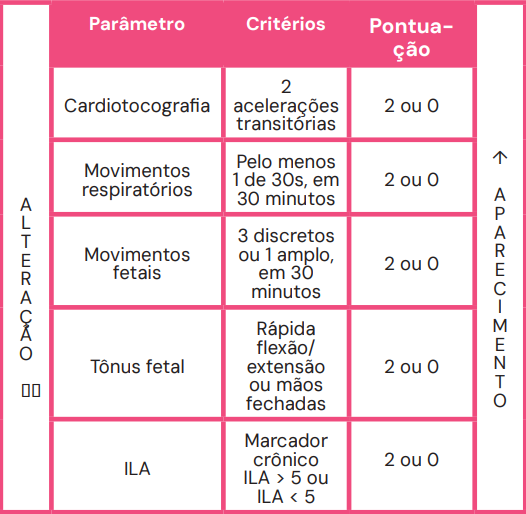

1. Perfil Biofísico Fetal (PBF)

O PBF avalia cinco parâmetros, atribuindo 2 pontos para normalidade e 0 para anormalidade:

- Marcadores Agudos: Cardiotocografia (reativa), movimentos respiratórios, movimentos corporais e tônus fetal.

- Marcador Crônico: Volume de líquido amniótico (maior bolsão > 2 cm). A redução da diurese fetal secundária à hipoxemia crônica leva ao oligoâmnio, tornando este um marcador de cronicidade.

A pontuação final guia a conduta: um resultado de 8 ou 10 é tranquilizador, enquanto pontuações de 4 ou menos indicam alta probabilidade de asfixia e geralmente levam ao parto. Uma pontuação de 8/10 com oligoâmnio sugere provável hipóxia crônica.